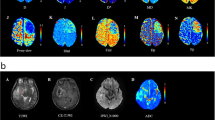

Included were 71 glioma patients (mean age, 50.17 ± 13.38 years; 35 men). HM-MRI images were collected at five different echo times (80–200 ms) with seven b-values (0–3000 s/mm2). A modified three-compartment model with very-slow, slow and fast diffusion components was applied to calculate HM-MRI metrics, including fractions, diffusion coefficients and T2 values of each component. Pearson correlation analysis was performed between HM-MRI derived fractions and H&E staining derived percentages. HM-MRI metrics were compared between high-grade and low-grade gliomas, and between IDH-wild and IDH-mutant gliomas. Using receiver operational characteristic (ROC) analysis, the diagnostic performance of HM-MRI in grading and genotyping was compared with mono-exponential models.

HM-MRI metrics FDvery-slow and FDslow demonstrated a significant correlation with the H&E staining results (p < .05). Besides, FDvery-slow showed the highest area under ROC curve (AUC = 0.854) for grading, while Dslow showed the highest AUC (0.845) for genotyping. Furthermore, a combination of HM-MRI metrics FDvery-slow and T2Dslow improved the diagnostic performance for grading (AUC = 0.876).